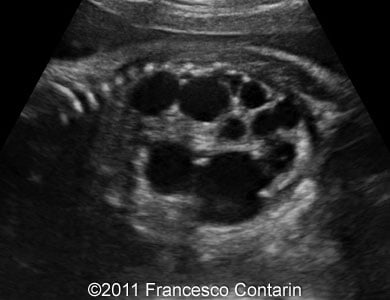

This is a case of a 24-year-old G3P2, with non contributive history, who was scanned at 32 weeks of gestation. Unilateral fetal multicystic kidney disease was found.

Images 1, 2, 3, and 4: The images show a series of longitudinal and transverse scans of the multicystic fetal kidney obtained at 32 weeks of pregnancy.